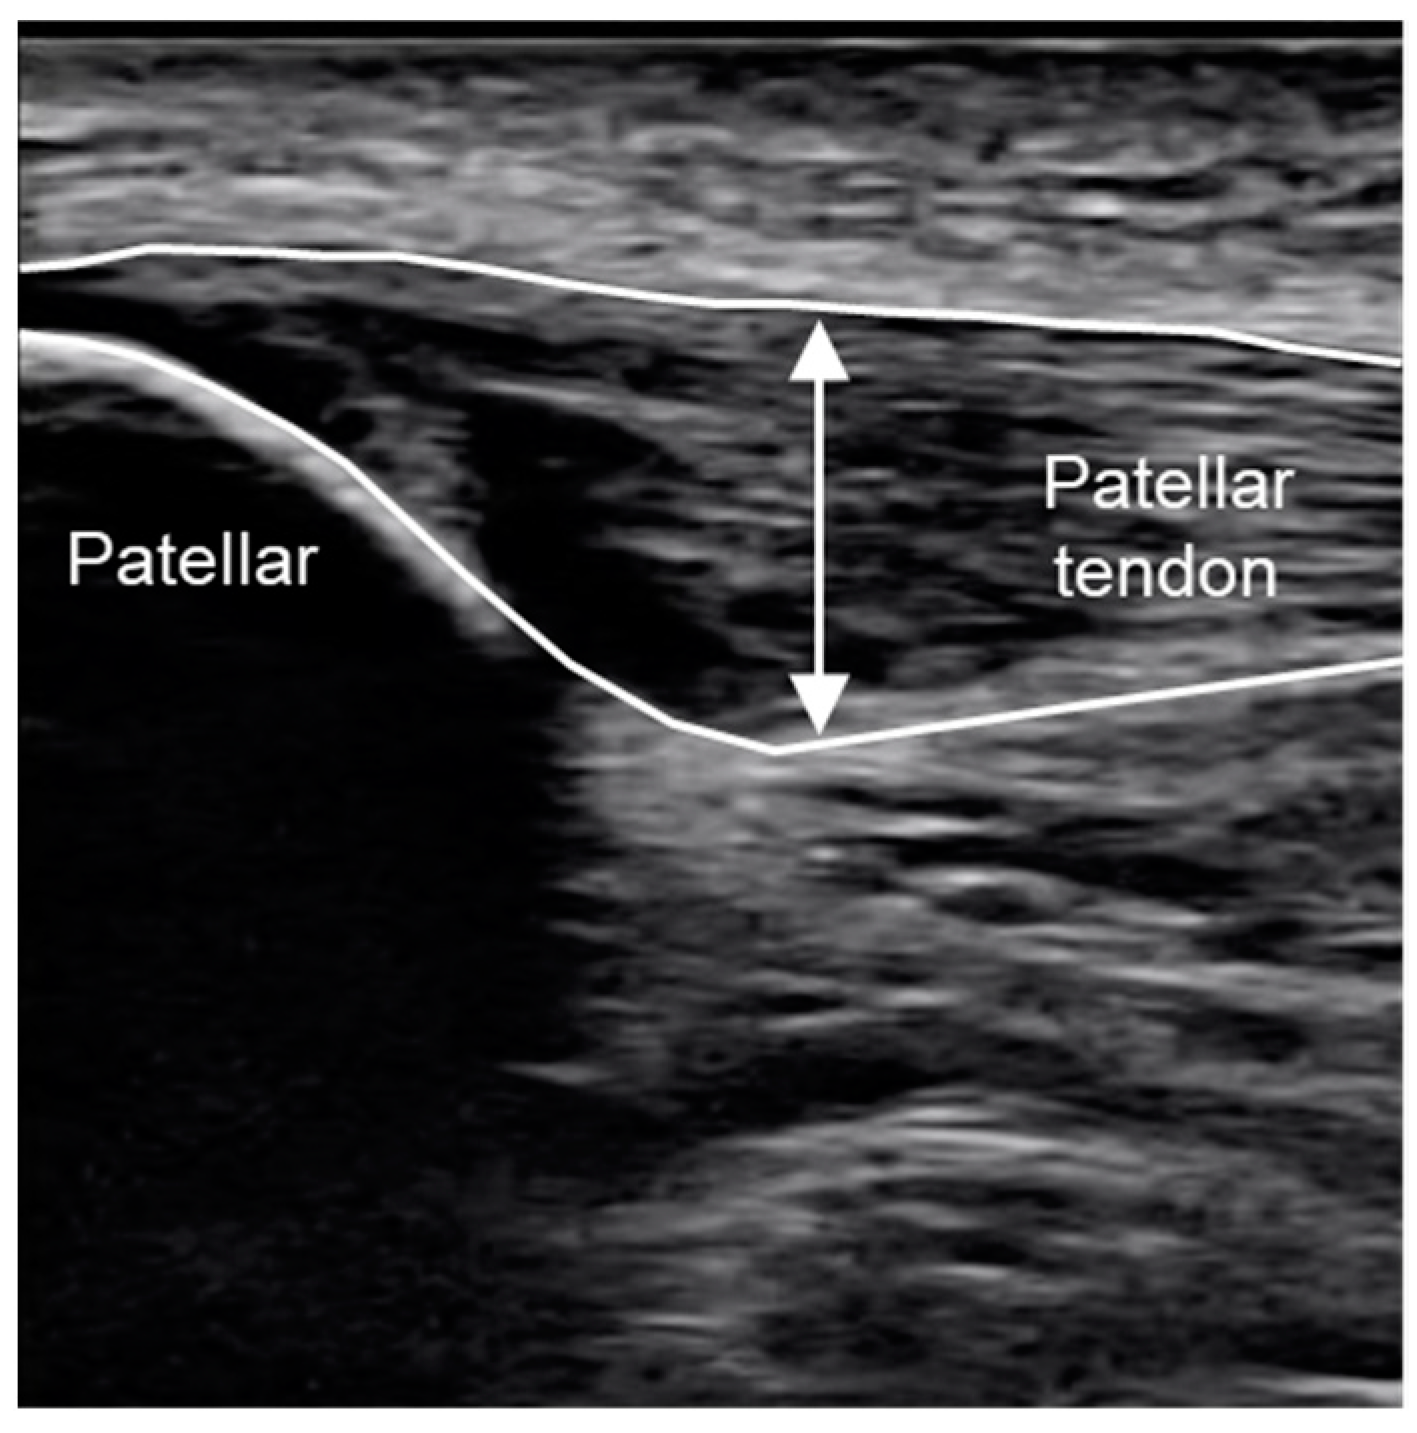

We used an extracorporeal shock wave pain treatment device (STORZ Medical, UK) to deliver the f-ESWT to the pain-inducing area. We gradually increased the f-ESWT energy transfer in the range of 0.01–0.25 mJ/mm2 according to the pain, delivering 2500 shots per session for 4 Hz. The subjects were irradiated with f-ESWT twice, at the beginning of the study and after 2 weeks. We evaluated the pain, rest pain and tenderness of the patellar tendon. Rest pain was mapped on the Numeric Rating Scale (NRS) [30] and the degree of pain was rated on 11 levels. We then used a pressure pain meter (FP meter, SN-402, Navis, Japan) to evaluate the pressure pain and recorded the pressure value at the time the participant experienced pain [31,32,33]. When the pressure pain meter was applied to the pain area and pushed in, the value increased from 0 to 10 (kg). The examiner pushed it in until the study participant felt pain and recorded the value at the time of pain as the pressure value. In other words, it was shown that the higher pressure value indicated a decrease in pain. To examine the effect of f-ESWT on the affected area, we evaluated the tendon thickness and blood flow of the patellar tendon using an ultrasound imaging system, Toshiba Aplio scanning machine (Canon Medical Systems Corporation, Japan). Ultrasound evaluations of the tendon thickness and blood flow were performed in the long axis direction using an ultrasonography device equipped with a high-frequency (5–14 MHz) linear probe. To measure the tendon thickness (mm), we recorded a still image of the area of maximum swelling using B-mode (Figure 1). For blood flow evaluation (Doppler), we recorded still images during the beating phase when the blood flow area was large (cm2). Each image was captured by an orthopaedic surgeon who examined the subject and selected the images to be used. Four sessions in total were taken for evaluation by the ultrasound imaging system before and after the f-ESWT in each subject. Three images of tendon thickness and blood flow evaluation were recorded in each imaging session, and the average of the 3 images was adopted as the value. These recorded images were used to calculate the blood flow area on the ultrasound image using the open-access image analysis software Fiji (Fiji is Just ImageJ) (Figure 2). The shock wave irradiation site, pain evaluation site and ultrasound evaluation site were evaluated and determined by a physician using an ultrasound imaging device, and markings were applied thus that measurements could be performed at the same site. The measurements were performed 4 times: before f-ESWT (PRE①), immediately after f-ESWT (POST①), before f-ESWT 2 weeks after the first f-ESWT (PRE②) and immediately after the second f-ESWT (POST②).

Figure 1.

Measurement for Patellar tendon thickness.